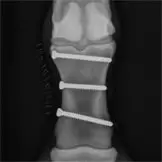

Griffelbeinfrakturen sind die am häufigsten auftretenden Frakturen beim Pferd. Hier ist die Prognose nach einer Operation in der Regel günstig, weil das Röhrbein die Hauptlast der Gliedmaße trägt. In der Regel wird hier das blind endende untere Fragment des Griffelbeins amputiert. Bei geschlossenen Frakturen im oberen Drittel des Griffelbeines kann eine Versorgung mittels Plattenosteosynthese sinnvoll sein. Offene Griffelbeinfrakturen im unteren Bereich können normalerweise erfolgreich operativ versorgt werden, offene Frakturen im Griffelbeinkopfbereich werden meist nicht chirurgisch behandelt, sondern müssen selbsständig abheilen. In selten Fällen kann auch eine Totalresektion eines Griffelbeins unumgänglich sein.